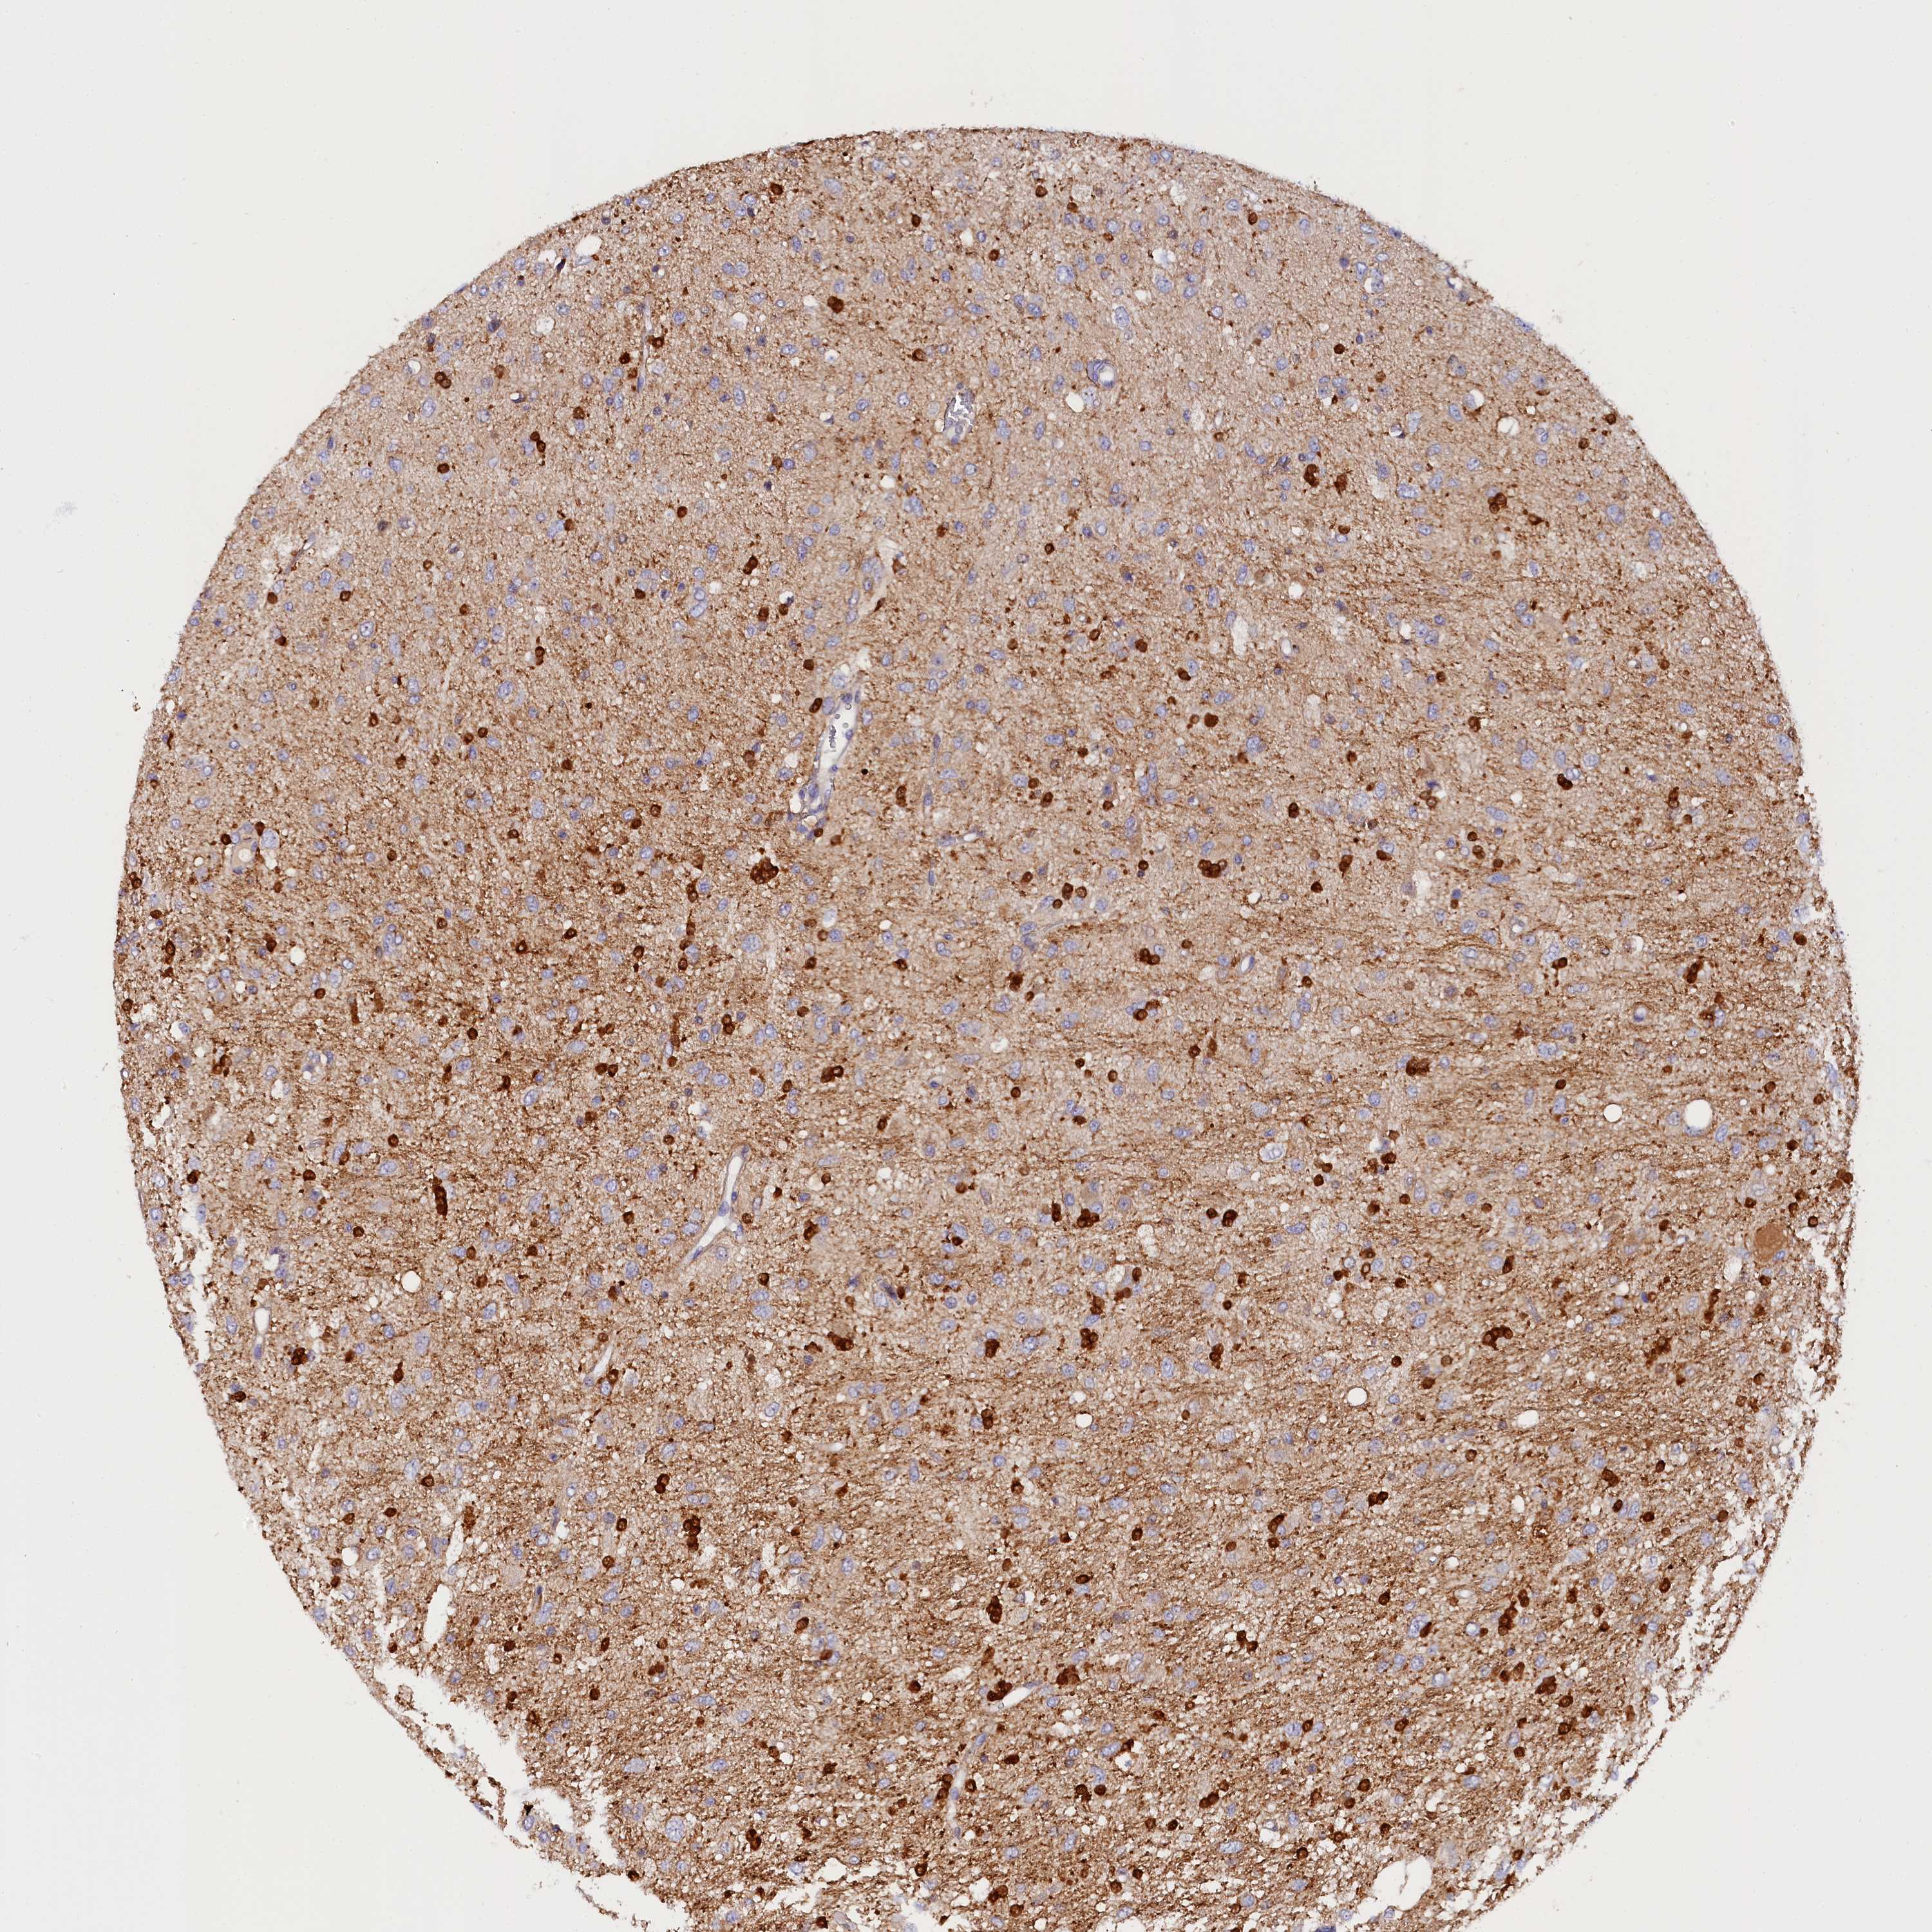

GLIOMA - Protein expressioni

A mouse-over function shows sample information and annotation data. Click on an image to view it in a full screen mode. Samples can be filtered based on level of antibody staining by selecting one or several of the following categories: high, medium, low and not detected. The assay and annotation is described here.

Note that samples used for immunohistochemistry by the Human Protein Atlas do not correspond to samples in the TCGA dataset.

Antibody stainingi

Antibody staining in the annotated cell types in the current human tissue is reported as not detected, low, medium, or high, based on conventional immunohistochemistry profiling in selected tissues. This score is based on the combination of the staining intensity and fraction of stained cells.

Each image is clickable and will lead to virtual microscopy that enables deeper exploration of all samples and also displays staining intensity scores, fraction scores and subcellular localization as well as patient and tissue information for each sample.

Antibody HPA041165

Antibody HPA041839

Staining

High

Medium

Low

Not detected

Intensity

Strong

Moderate

Weak

Negative

Quantity

>75%

75%-25%

<25%

None

Location

Nuclear

Cytoplasmic/membranous

Cytoplasmic/membranous,nuclear

Glioma, malignant, High grade

Glioma, malignant, Low grade